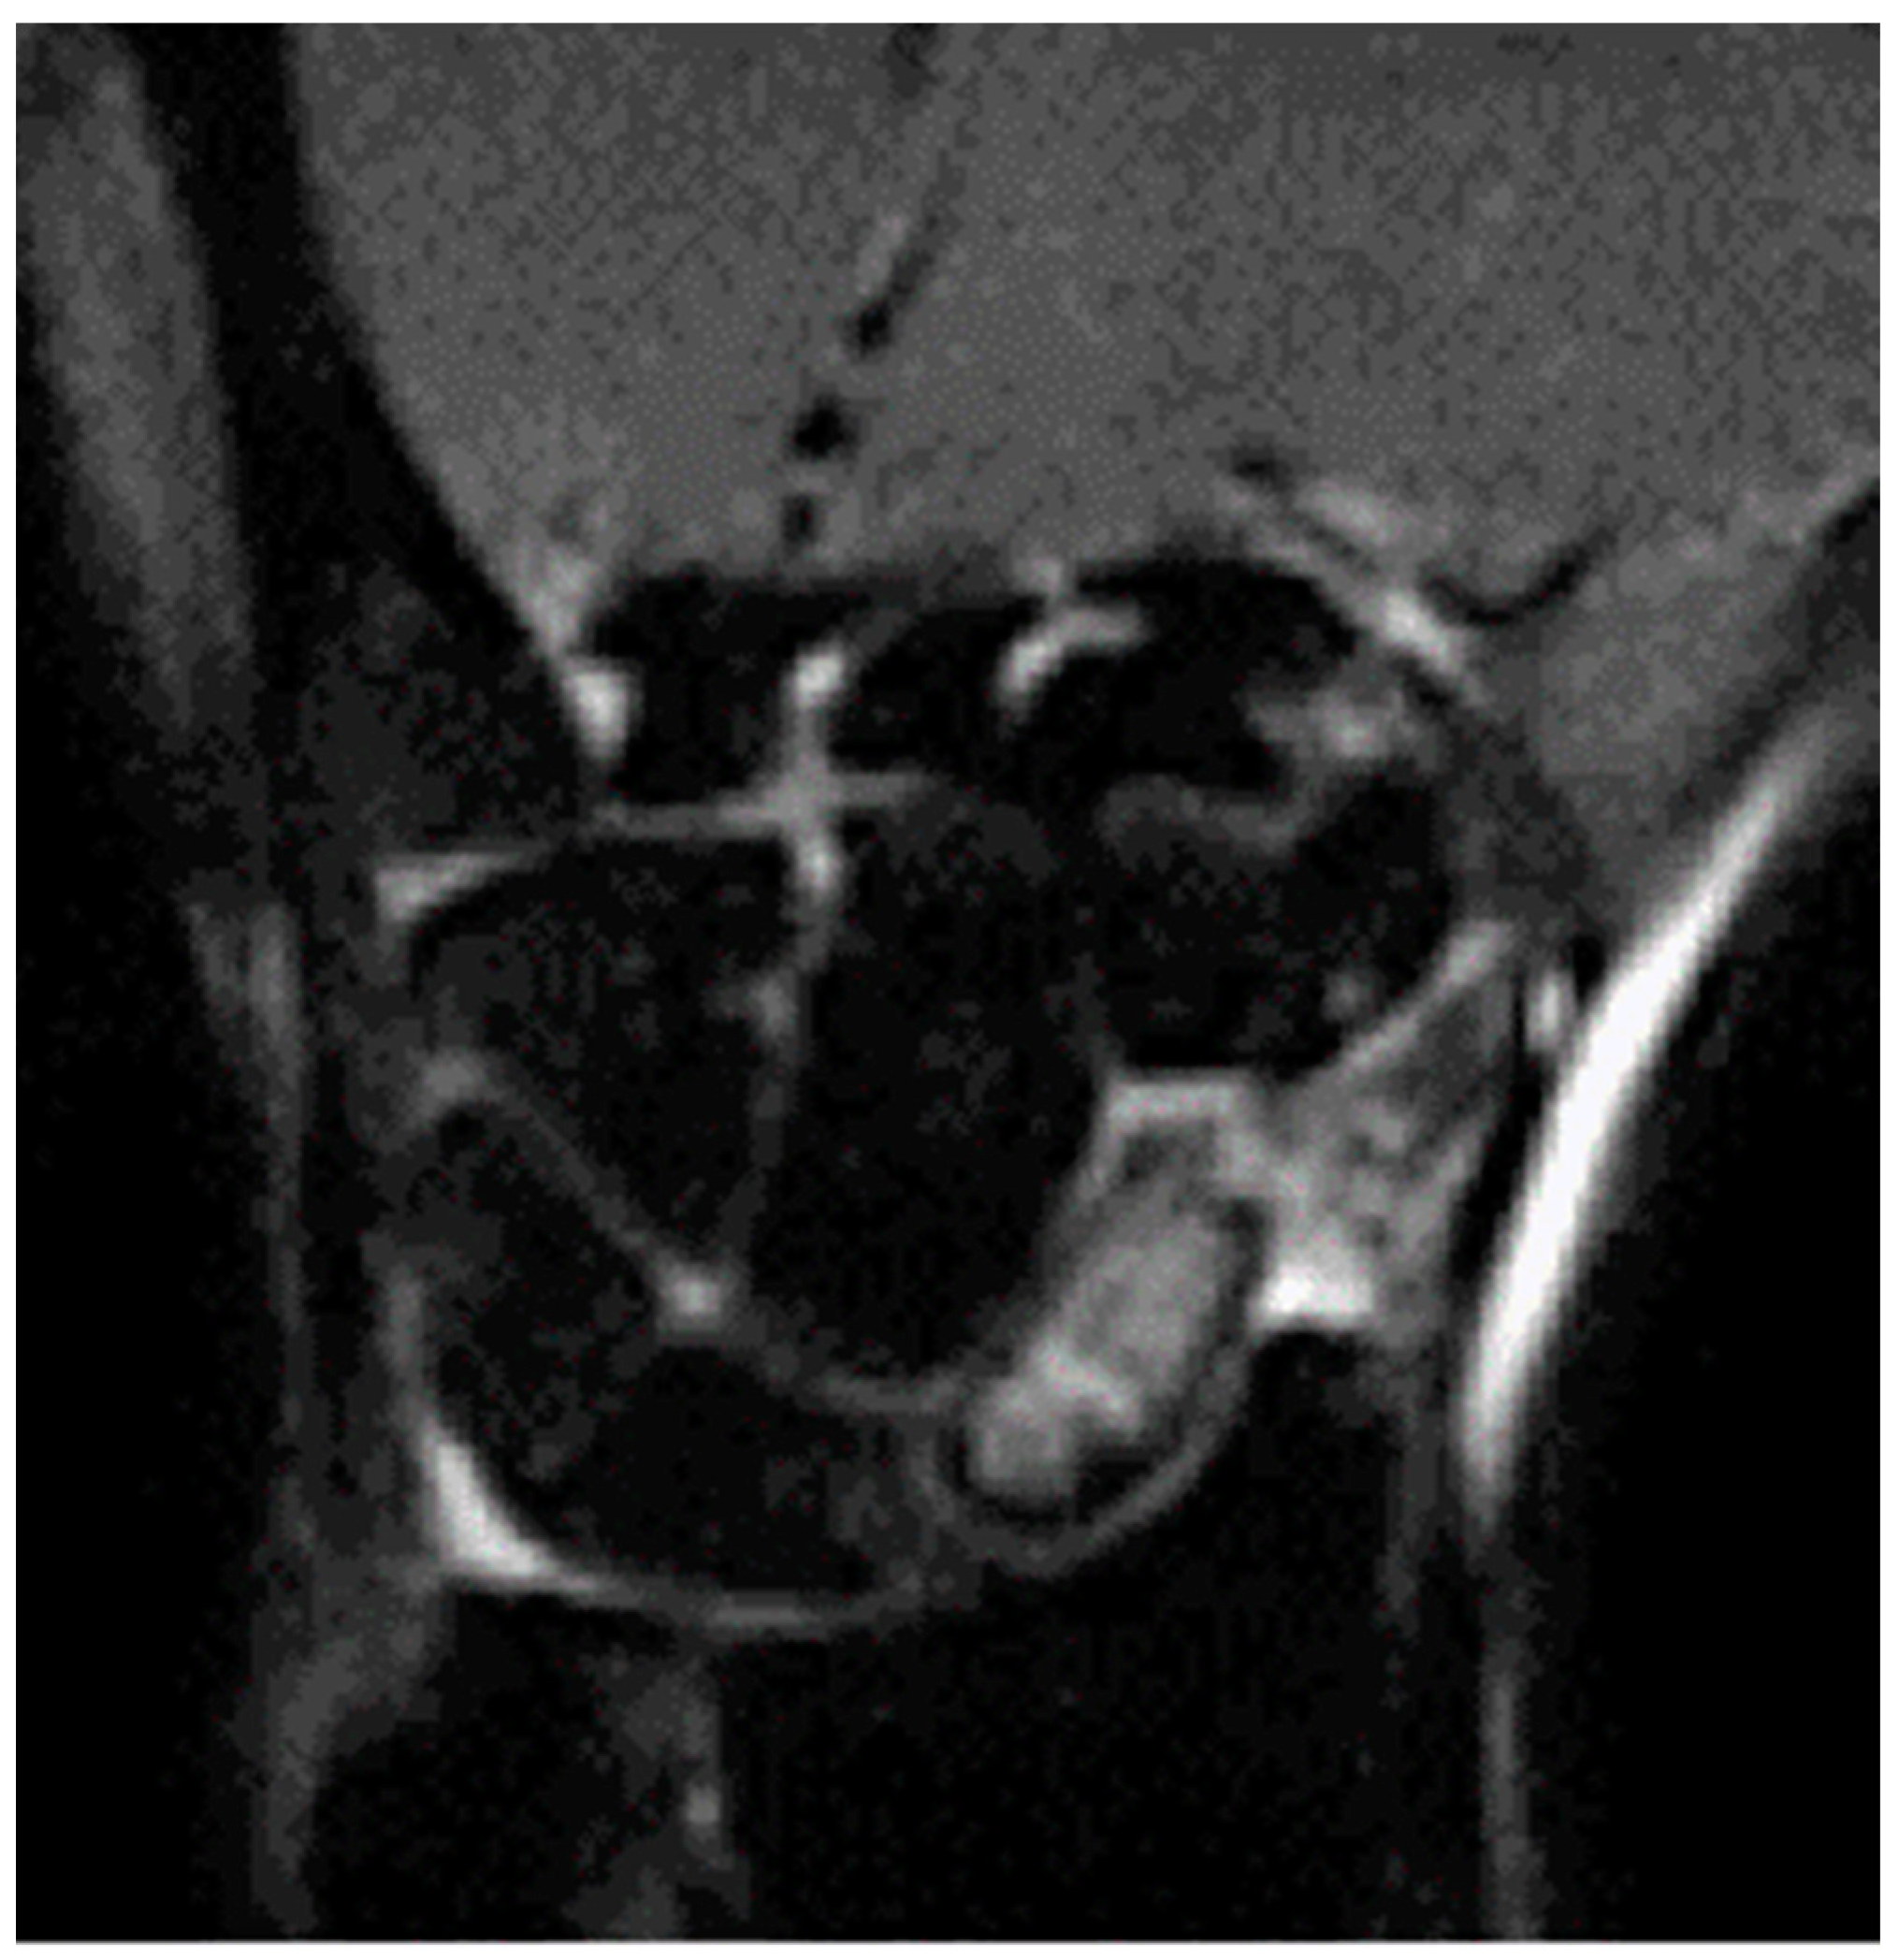

2.4. Surgical Technique